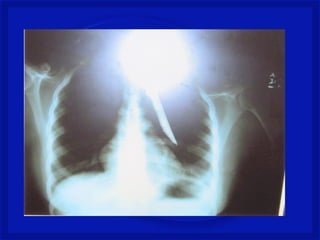

Registro fotográfico Pessoal

Medular Penetrante

•Perfuração da coluna (arma branca, tiro

ou estilhaço de bomba na coluna)

•Lesão medular completa ou incompleta,

associada ou não a lesão dos nervos

espinhais e/ou tronco dos plexos

nervosos.

•Quadro neurológico é variável.